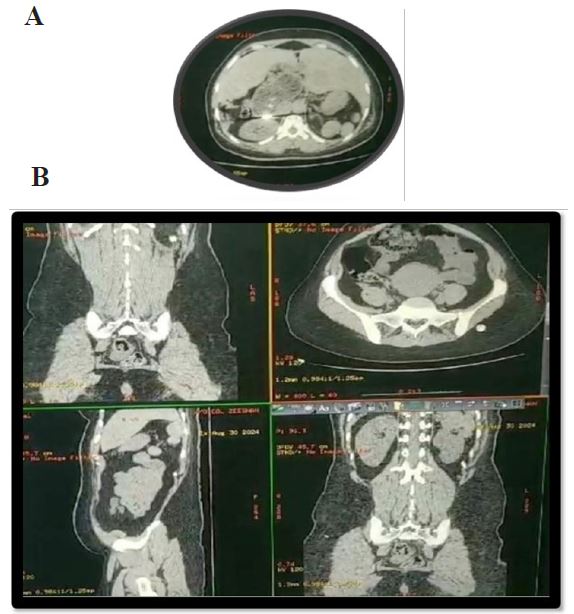

As shown in figure 2a & b below.

Figure 2: (A) CECT axial cut showing polysplenia; (B) CECT showing malrotation of gut, dilatation of duodenum and polysplenia.